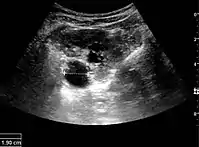

Figure 5. Simple renal cyst with posterior enhancement in an adult kidney. Measurement of kidney length on the US image is illustrated by '+' and a dashed line.[1]